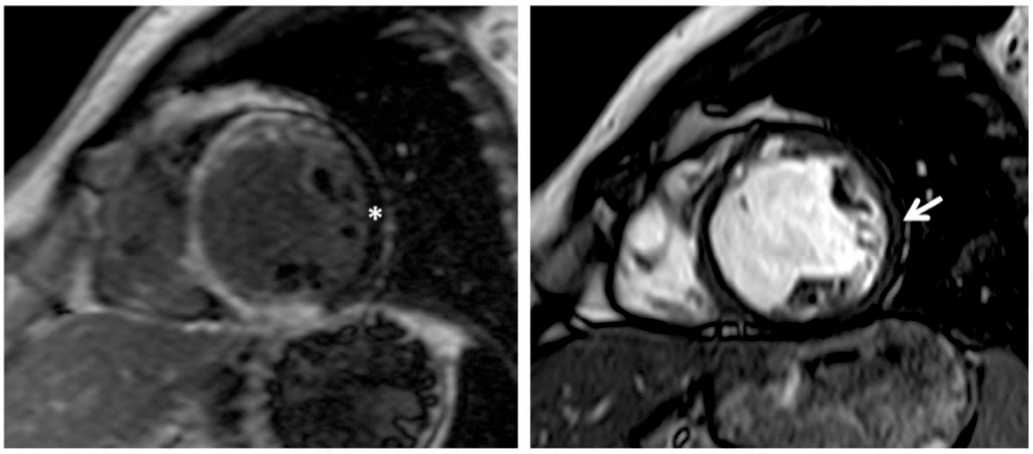

Рис. 2. Магнитно-резонансная томография сердца, Пациент Л., возраст 61 год, с ишемической кардиомиопатией. А – отсроченное контрастирование, короткая ось; Б – кино-режим, SSFP последовательность: короткая ось, диастола. Отмечается трансмуральное накопление контрастного вещества по нижней, передней стенкам левого желудочка и межжелудочковой перегородке; в проекции боковой стенки левого желудочка данных за ишемическое повреждение миокарда нет. На изображениях магнитно-резонансной томографии сердца в кино-режиме формируется зона интереса в области боковой стенки (стрелка), что соответствует визуально интактному миокарду на изображении с отсроченным контрастированием (звездочка)

Fig. 2. Cardiac MRI in Patient L., 61, with ischemic cardiomyopathy. A – late gadolinium enhancement (LGE) short-axis view; B – cine mode, SSFP sequence: short-axis view (diastolic phase). Transmural LGE is observed in the inferior and anterior left ventricular (LV) walls and the interventricular septum. No evidence of ischemic injury is seen in the lateral LV wall. On the cine image the region of interest in the lateral wall (white arrow) corresponds to visually preserved myocardium on the LGE image (white asterisk)